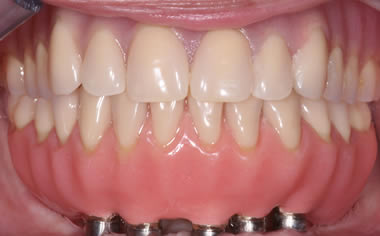

Full arches of teeth replaced by dental implants

Case Two (8 images)

Full set of lower teeth fixed onto five dental implants.